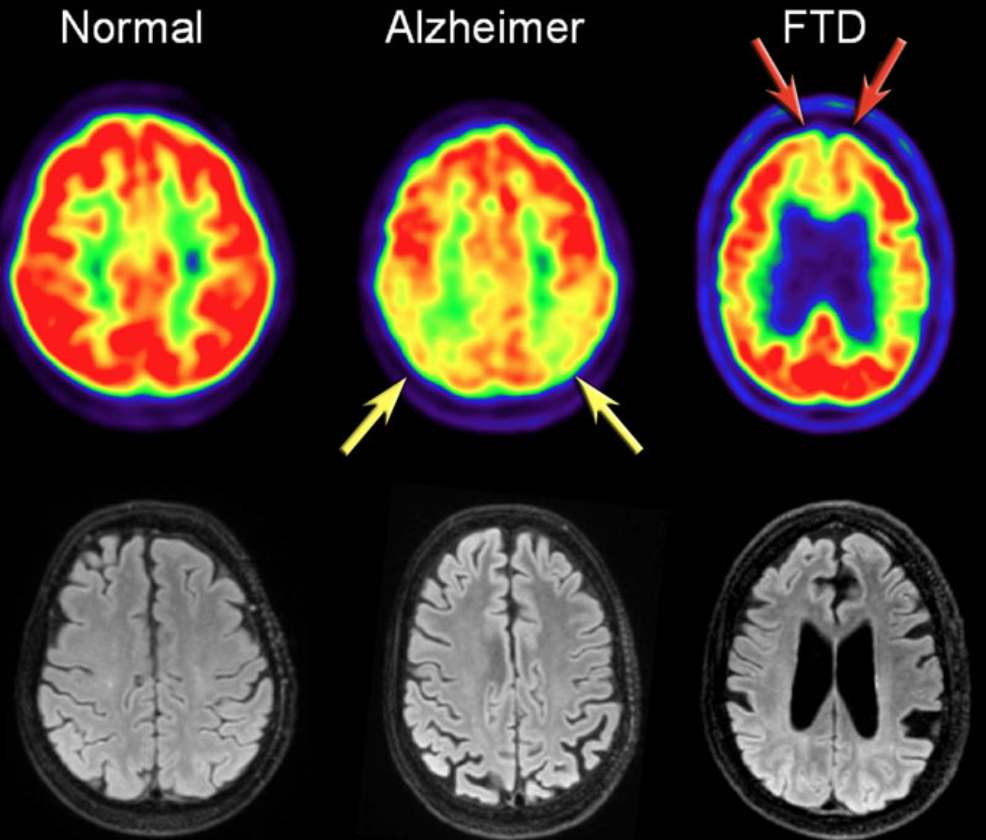

In addition to clinical findings, CSF and MRI, PET imaging are useful in diagnosing AD. In AD, FDG-PET can show hypometabolism in the temporoparietal regions and/or the posterior cingulum. This may help differentiate AD from FTD (Frontotemporal Dementia), which shows frontal hypometabolism on FDG-PET. The images show FDG-PET and axial FLAIR images of a normal subject and of patients with AD and FTD: FDG-PET (top row) and axial FLAIR images of a normal subject and of AD and FTD patients. In AD there is a decreased metabolism of the parietal lobes (yellow arrows), whereas in FTD, there is frontal hypometablism (red arrows).